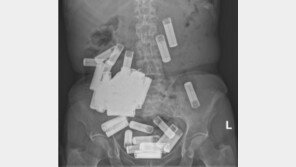

아일랜드에서 60대 여성이 수십 개의 건전지를 삼키는 괴이한 자해 행동을 해 충격을 주고 있다. 15일(현지시간) 아이리시 인디펜던트, 아이리시타임스 등의 보도에 따르면 66세의 한 여성이 더블린에 있는 세인트빈센트병원에서 배에 들어있는 50개의 배터리 제거 수술을 받았다. 이…